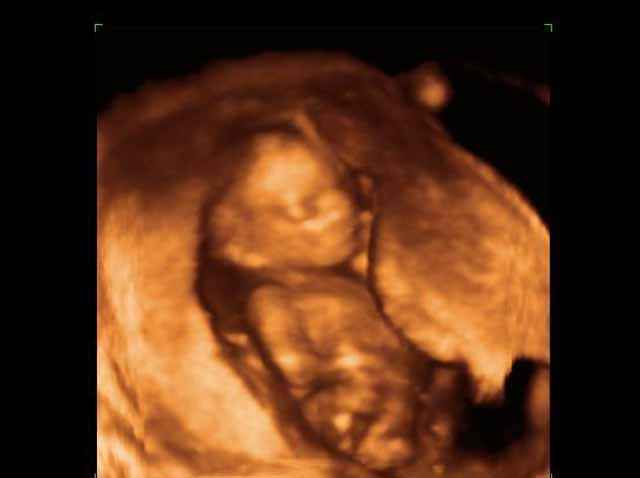

3D second trimestre échographie Photos de numérisation - deuxième partie de la grossesse | Dr N Layyous

3D second trimestre échographie Photos de numérisation - deuxième partie de la grossesse